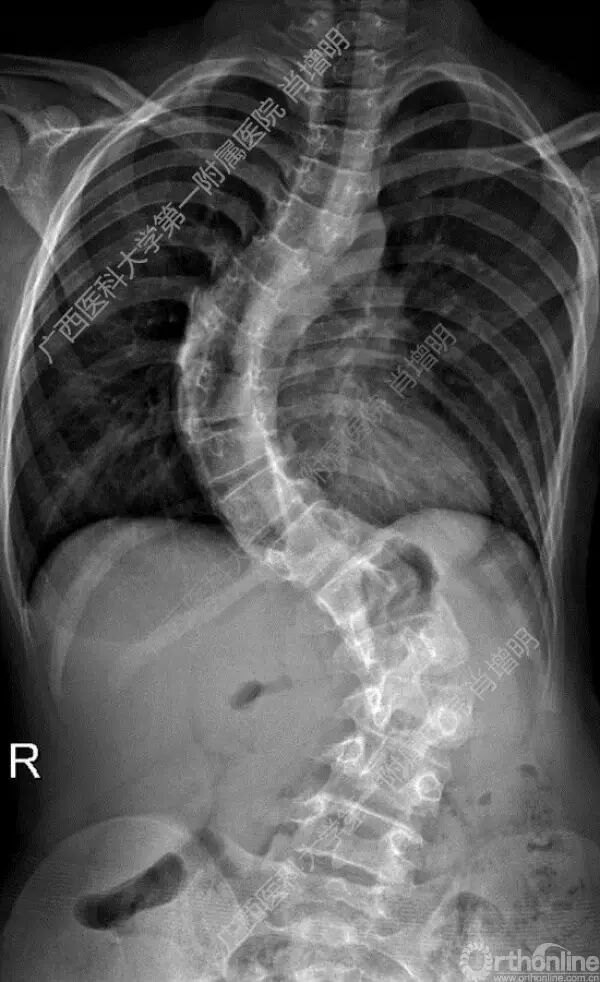

退变性脊柱侧凸是由于椎间盘退变后继发小关节退变,椎管和神经根管容积变化以及脊柱失稳,畸形等病理改变,以疼痛和神经压迫症状为主要表现的常见疾病。

退变性脊柱侧凸多发于50岁以上的中老年群体,是现代常见的老年疾病。多年来,针对该病的临床研究一直没有停步,广西医科大学第一附属医院肖增明教授细致地介绍了该病的诊疗进展。